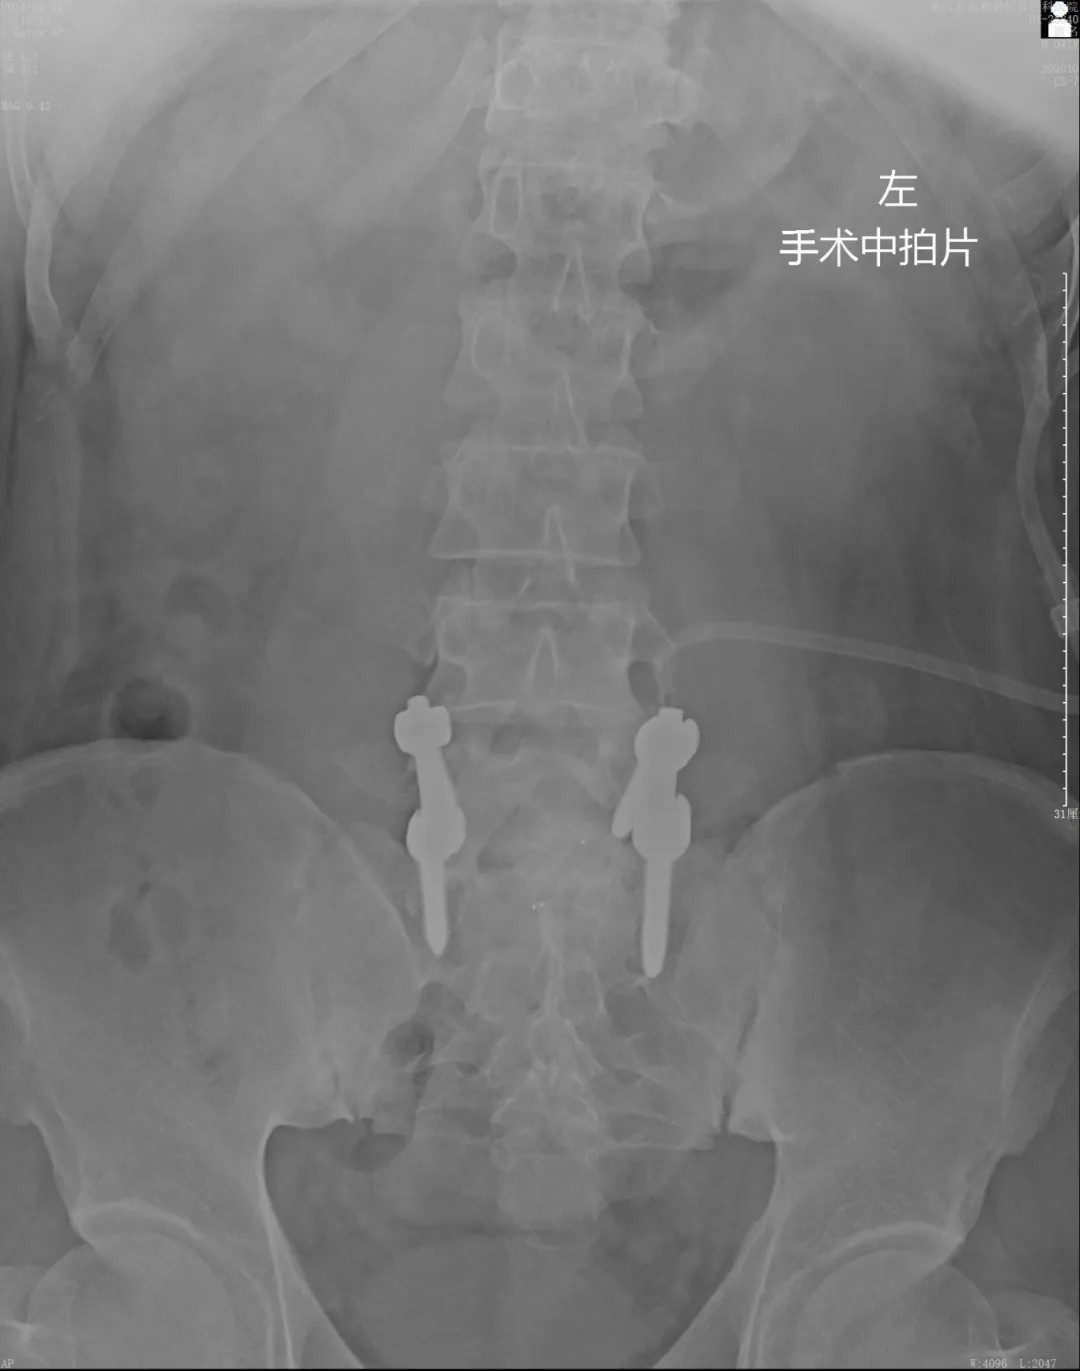

針對患者復(fù)雜的病情及二次翻修手術(shù)的情況,我院專家團(tuán)隊(duì)?wèi){借豐富的經(jīng)驗(yàn)、專業(yè)的技術(shù)、密切的配合,為患者在蔡司TIVATO 700手術(shù)顯微鏡下實(shí)施了腰椎融合術(shù)后翻修、融合內(nèi)固定微創(chuàng)手術(shù)。

手術(shù)全程使用術(shù)中電生理監(jiān)測系統(tǒng),每步都力求精準(zhǔn)細(xì)致。在解除原有問題的同時(shí),一定程度保護(hù)了周圍正常組織。經(jīng)過數(shù)小時(shí)的緊張操作,手術(shù)圓滿成功。